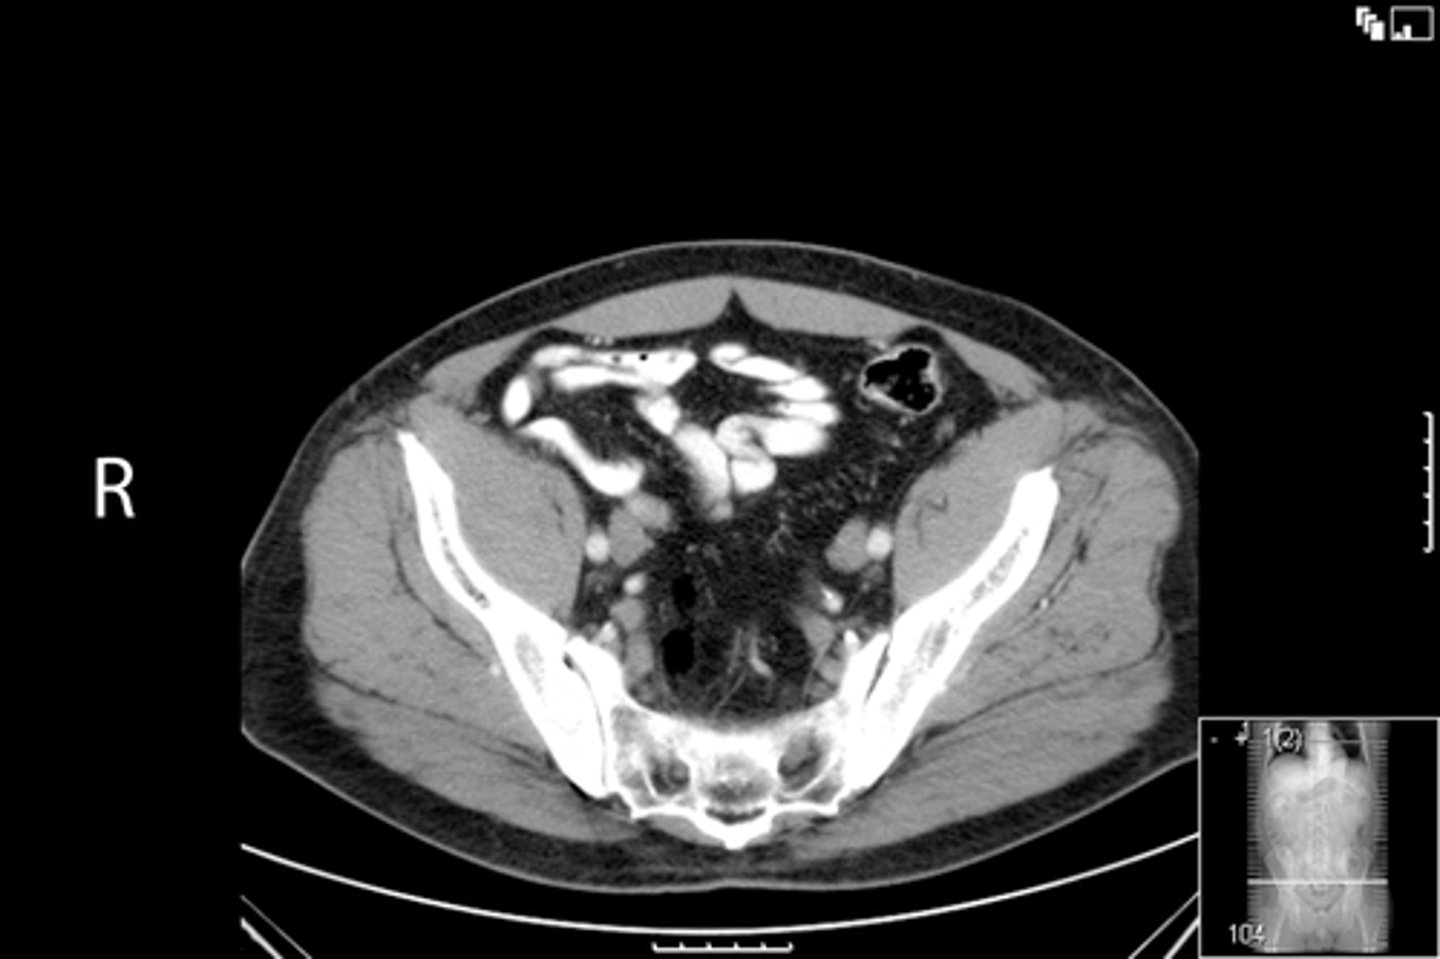

Axial bony pelvis CT

What is the image?

<p>What is the image?</p>

32

New cards

L ilium

What is indicated in the image?

<p>What is indicated in the image?</p>

33

L sacroiliac joint

34

R ilium

35

R sacroiliac joint

36

Sacrum